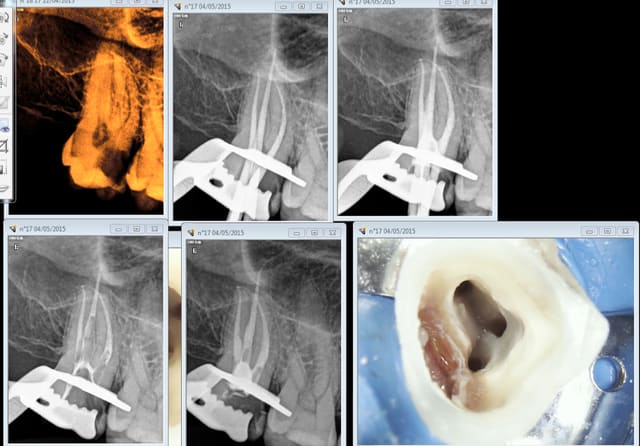

Ouais, je prend une heure pour l'endo molaire mais il me faut entre 30 et 40 mn pour la faire. Celle ci 30 mn.